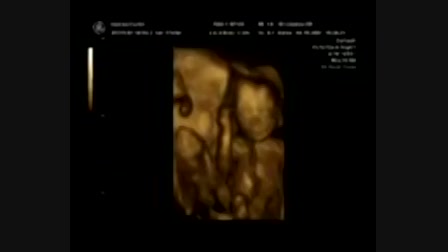

Prüntyi 4D ultrahang

bandita09

Date: 2008. 05. 16.